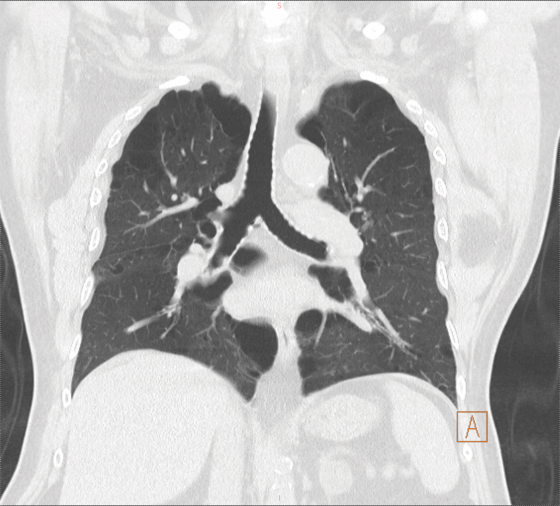

老王是个老烟民,40多年的烟龄,每天1-2包烟,一直没有间断。双肺满布大疱,肺气肿明显,肺功能结果非常差。并且老王缺乏锻炼,身形肥胖,170cm的身高,体重达到90kg,对肥胖患者而言,相对肺容积较小,这使本身就差的肺功能更显得捉襟见肘。

左图:术前冠脉造影(白色箭头指示前降支支架内严重狭窄) 右图:术前CT影像(双肺肺气肿、肺大疱)